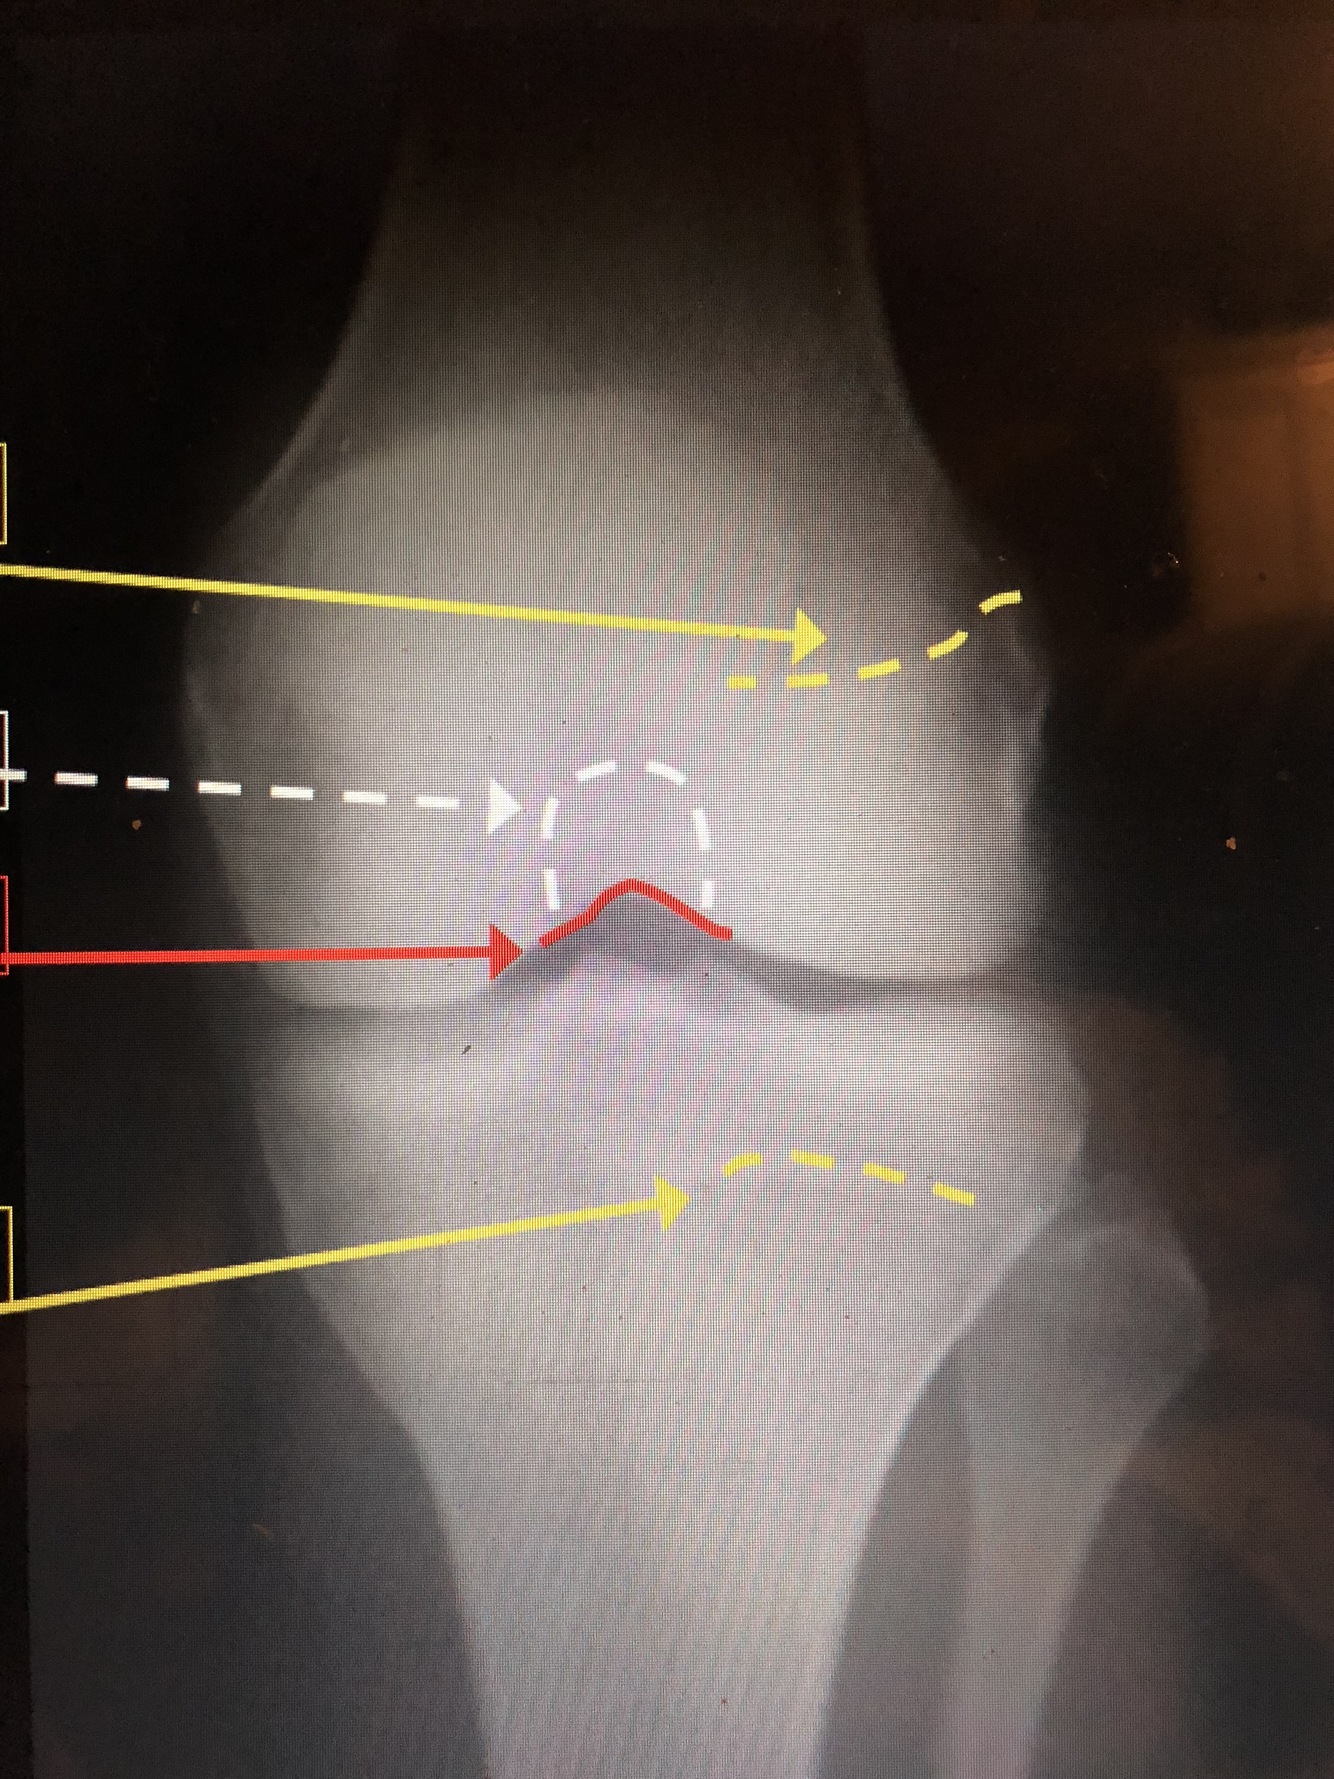

Q

Femoral Physeal Scar

Tibial Physeal Scar

Intercondylar Fossa

Intercondylar Notch

Popliteal Surface of the Femur

Ludloff’s Spot – area of lucency in condyles

Intercondylar Notch/Groove

Patellar Surface of the Femur

20

patella